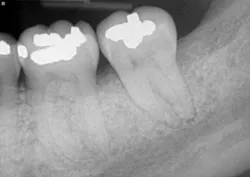

The patient returned after two weeks for a postoperative check of No. 31 and had a maintenance visit at three months post-op. At the three-month mark, the Visual-SRP area was evaluated for results. The pocket depth had resolved to 4 mm without signs of inflammation. A periapical radiograph of the area suggested bone remineralization in the site of No. 18 distal (figure 3). No. 31 was required to heal for six months and was not assessed until that time. At the six-month mark, the patient returned for another maintenance visit. The surgical area was measured, and the pocket depth had resolved to 4 mm without signs of inflammation. The periapical radiograph of No. 31 distal revealed the vertical defect was repaired, and new bone formation was evident (figure 4).

Figure 4: Periapical radiograph of No. 31 distal shows a repaired vertical defect and new bone formation, six months after treatment with periodontal pocket reduction surgery and bone regenerative materials